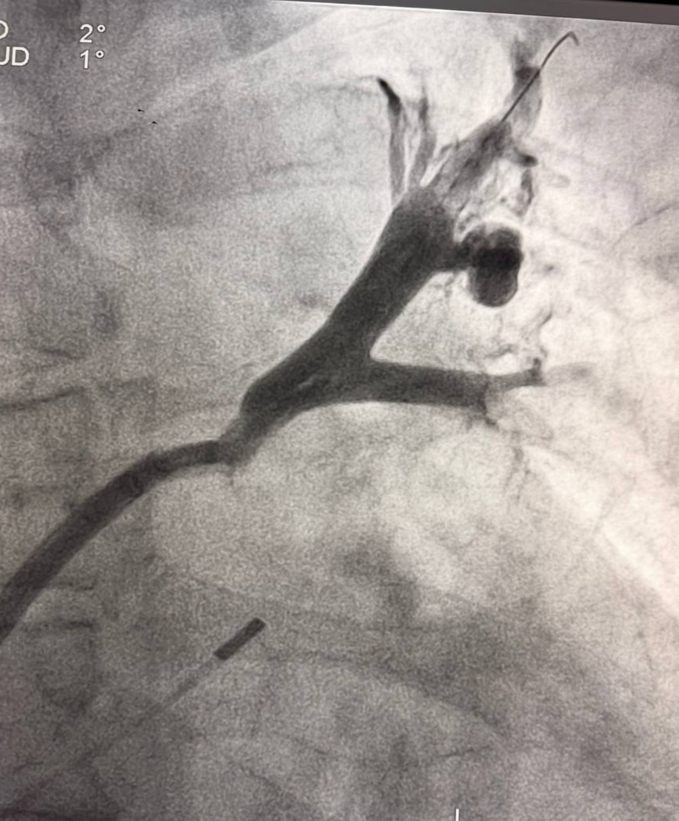

Пациент М., 54 лет наблюдался с длительной историей нарушений ритма сердца. Ранее ему была выполнена криоабляция, а спустя два года — радиочастотная абляция. Через два месяца после РЧА у пациента появились выраженная слабость и одышка при физической нагрузке. При дообследовании выявлены окклюзии левой верхней и левой нижней легочных вен.

Вмешательство проводилось через бедренный венозный доступ под местной анестезией. Основная сложность операции заключалась в полной окклюзии обеих легочных вен и необходимости точной навигации инструментов в условиях ограниченной визуализации. После реканализации поражённых участков были имплантированы стенты, обеспечившие надёжное восстановление просвета сосудов и полноценный венозный отток из лёгких.

В результате кровоток по левой верхней и левой нижней легочным венам полностью восстановлен. Состояние пациента стабилизировалось, одышка регрессировала. В настоящее время пациент чувствует себя хорошо.